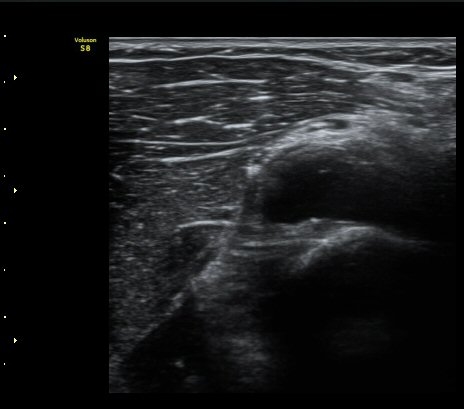

¼ÒµÎ Ⱦ´Ü¸é°Ë»ç¿¡¼­ ¿ä°ñ½Å°æ Èİñ°£½Å°æÀÌ Á¤»óÀûÀ¸·Î °í³ªÂûµÈ´Ù(±×¸² 1).

ŽÃËÀÚ¸¦ ¿ä°ñµÎ ºÎÀ§·Î À̵¿ÇÏ´Ï ¿ä°ñµÎ Ç¥Ãþ¿¡ Àú¿¡ÄÚ ³¶Á¾ÀÌ °üÂûµÇ°í ³¶Á¾ÀÇ ¿ÜÃø¿¡¼­

Èİñ°£½Å°æÀÌ ¾Ð¹ÚµÇ°í ÀÖ´Ù(±×¸² 2).